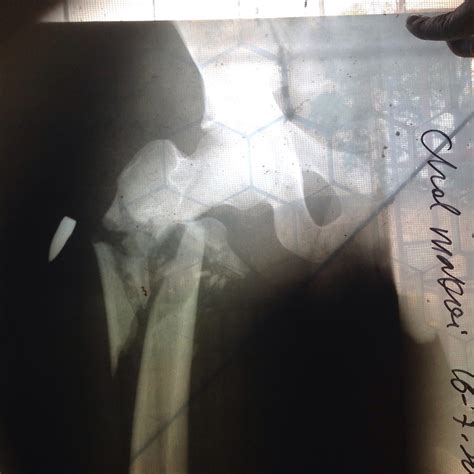

• Imaging studies, such as X-rays or CT scans, to determine the extent of the damage and the location of the bullet.